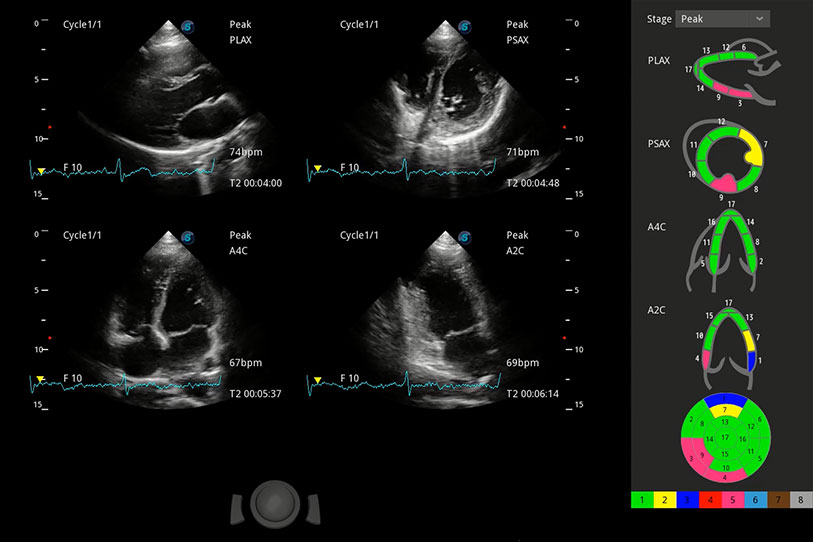

能夠基于左心室壁追蹤和辛普森法,自動計(jì)算射血分?jǐn)?shù),支持多個(gè)可移動點(diǎn)描跡,與手動測量相比,極大節(jié)省了動物醫(yī)生的時(shí)間和精力。

具備多種協(xié)議可選,同時(shí)支持17階段劃分法和專業(yè)的SE報(bào)告。